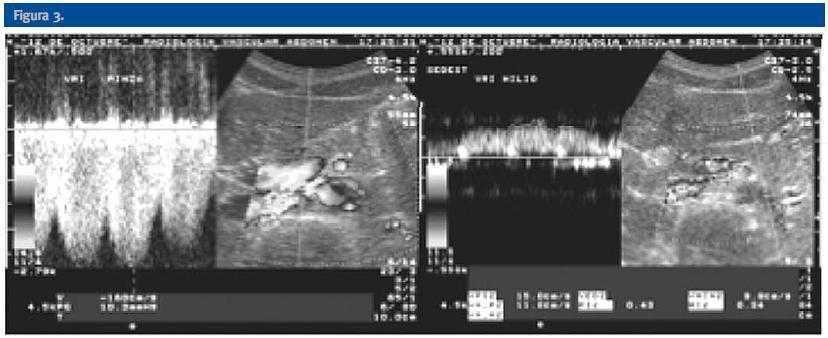

Mujer de 29 años de edad remitida desde Atención Primaria para estudio de microhematuria. Presentaba antecedentes de asma bronquial en tratamiento con inhaladores. A la exploración física se evidenciaba presión arterial normal y hábito asténico (Peso: 47 Kg; Talla: 162 cm; IMC: 17,9 Kg/m2). La enferma refería clínica de larga evolución consistente en astenia y dolor recidivante en flanco izquierdo que se intensificaba durante el ejercicio físico. A lo largo de su seguimiento presentó dos episodios de hematuria macroscópica de 4 y 10 días de evolución sin relación con cuadros infecciosos. En las pruebas complementarias iniciales presentaba función renal normal con proteinuria de 0,3 g/d y sedimento con microhematuria mantenida (15-20 hematíes por campo) aunque sin hematíes dismórficos. Las eliminaciones urinarias de calcio, fósforo, ácido úrico, oxálico y magnesio fueron normales. La citología urinaria para células malignas fue negativa. En el estudio inmunológico no se apreció ningún dato anormal (Tabla 1). La ecografía abdominal y la urografía intravenosa no revelaron ninguna alteración de interés. Ante la normalidad de estas pruebas radiológicas se realizó ecografía Doppler color renal y tomografía computarizada (TC) (figs 1,2 y 3).

La ecografía Doppler, al igual que la TC realizada, demostró la compresión de la vena renal izquierda entre la arteria mesentérica superior (AMS) y la aorta abdominal (A). En la ecografía Doppler se demostraba un efecto de pinza sobre la vena renal principal izquierda (VRI) que se traducía en una asimetría de flujo venoso entre ambos riñones, siendo de amplitud y pulsatibilidad disminuída en el lado izquierdo. Se observaba también circulación colateral retroaórtica (CCR) con inversión de flujo en la vena ovárica izquierda. En la TC se evidenciaba circulación colateral retroaórtica (vena renal retroaórtica accesoria).

Figura 3.